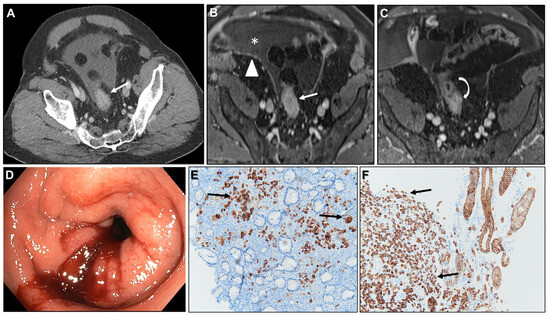

Malignant Target Sign

Homogeneous Delayed Enhancement

Concentric Ring Pattern

2.3.4. Pathology